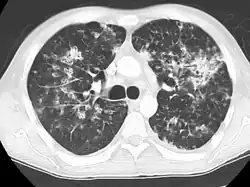

A case of miliary tuberculosis in an 82-year-old woman:

-

CT, 16 days after onset, showing extensive pulmonary parenchymal involvement consisting of irregular septal thickenings with ground-glass areas and centrilobular nodules with a peri-lymphatic distribution -